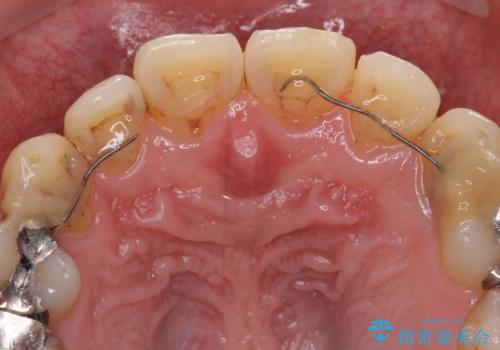

- 以前矯正を行った際に前歯が虫歯だらけとなり、審美面を気にして来院された患者様です。

虫歯の大きかった左右犬歯はオールセラミッククラウンで補綴治療をおこない、4前歯は研磨や古い充填物の詰め直しを行いました。